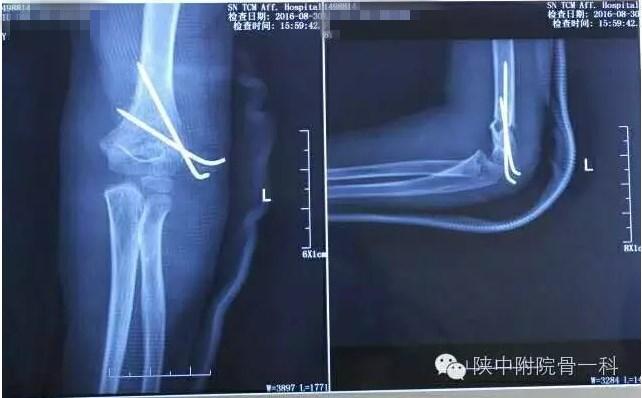

肱骨髁上骨折闭合复位手术记录,小儿肱骨髁上骨折手术恢复的概率 病案一:患儿XX,女,8岁,摔伤后左肘关节疼痛伴活动受限3小时入院。

肱骨髁上骨折闭合复位手术记录,小儿肱骨髁上骨折手术恢复的概率 诊断:Gartland Ⅱ型骨折

急诊行闭合手法复位克氏针内固定,术后X线片(下图)